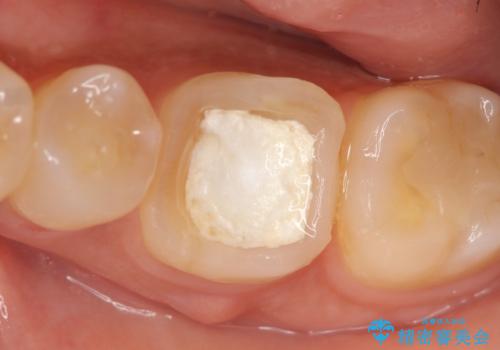

- 他院にて左下6の治療をしていたが、症状が引かないため当院にいらっしゃった方の症例です。

検査の結果左下6は神経が死んでいたため、根管治療を行いました。

その後症状の緩解を確認後、オールセラミッククラウンによる補綴を行いました。